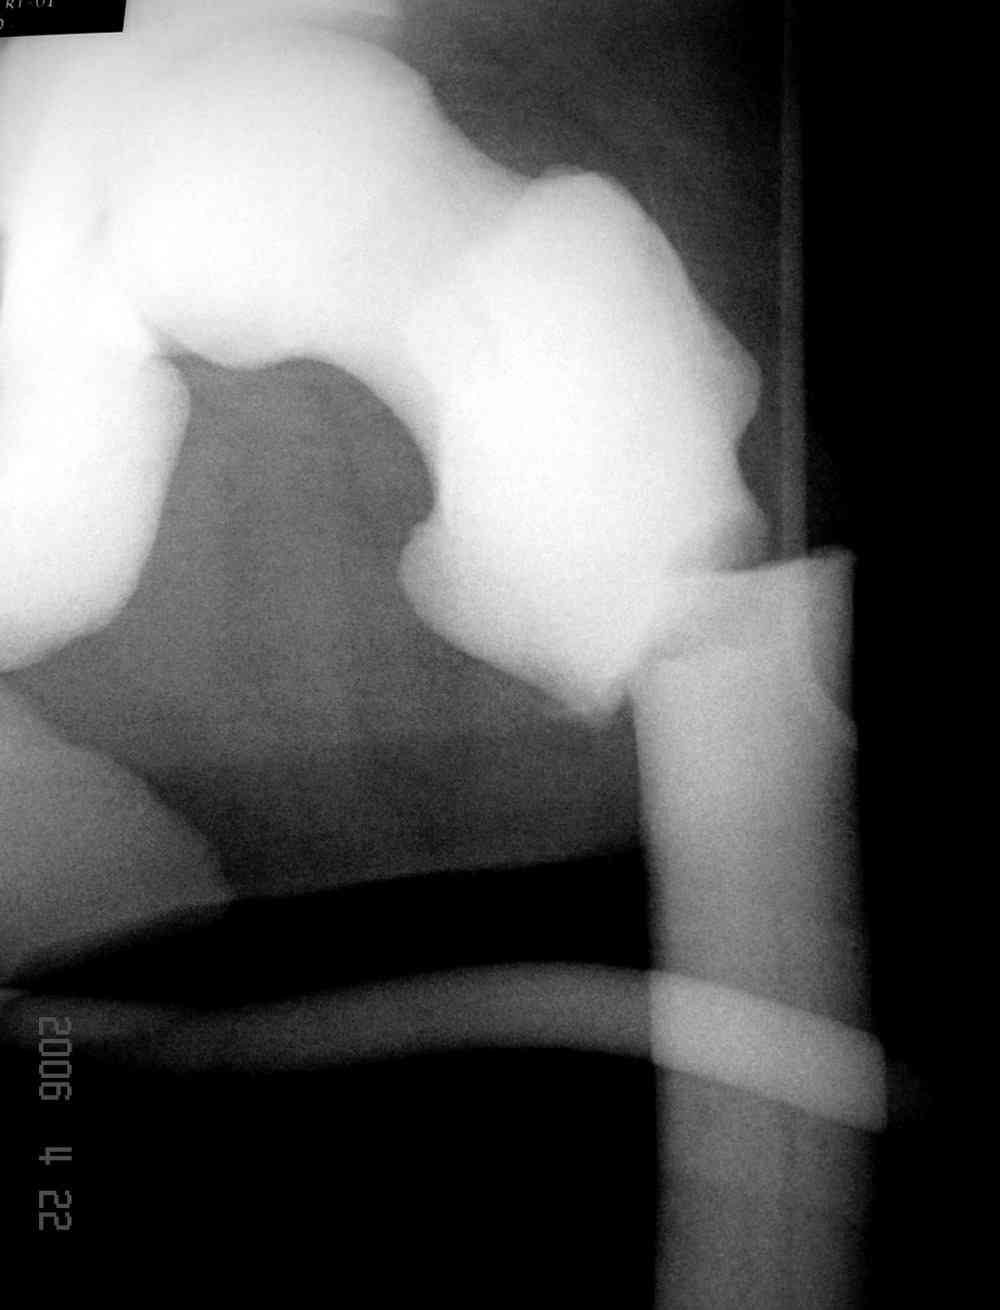

Остеопетроз характеризуется болями в костях, а на ренгене следы множественных несращении длинных трубчатых костей и “белая-мелоподобная” кость.

Не являюсь специалистом по костной патологии, но мне кажется, на ренгенограмме множественные мета-диафизарные образования напоминяющее змееподобных извилистых линии и периостеальные ламинирование очень напоминяет картину остеонекроза (инфаркта) костей, возможно связано с длительным применением стероидов.

слайды из прошлегодного случая.

Djoldas Kuldjanov, MD

Department of Orthopedic Surgery

St. Louis University Medical Center